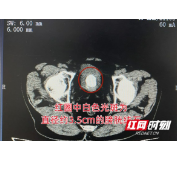

张嗲嗲术前CT检查局部图。

据长沙京石医院院长/泌尿外科主任卢卓雄介绍:“根据患者的检查报告,我们发现他的病情主要有两个问题,一个是膀胱内3.5cm的巨型结石,另一个则是前列腺增生明显问题。虽然当务之急是首先处理膀胱结石,但如果不一并处理前列腺增生的话,后期膀胱内还是会容易出现尿液残留,从而增大膀胱结石复发几率。”